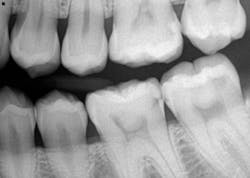

A 26-YEAR-OLD FEMALE PRESENTS for a new-patient exam. She had already been seen for a limited exam and subsequent extraction of a wisdom tooth. She was diagnosed with generalized Class II periodontal disease and multiple restorative needs, including gross apple-core and interproximal caries. It is highly likely that several teeth will end up needing crowns and possible root canals. However, due to the extent of perio, the immediate goal is to stabilize and arrest the caries. Restoring form and function will soon follow. See Figures 1 and 2.